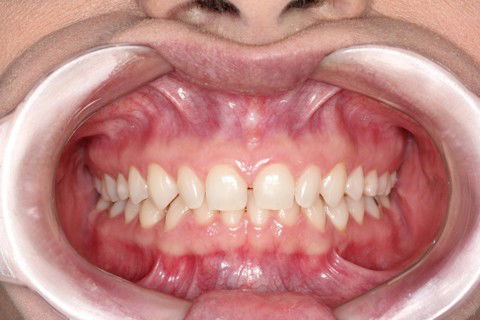

Resultado final

Sugestão de Tratamento: 10 Laminados cerâmicos (Lentes de Contato Dentais), no arco superior contemplando os elementos dentários 15,14,13,12,11,21,22,23,24 e 25.

5º Passo: Cimentação + Checklist Oclusal + Fotografias finais.